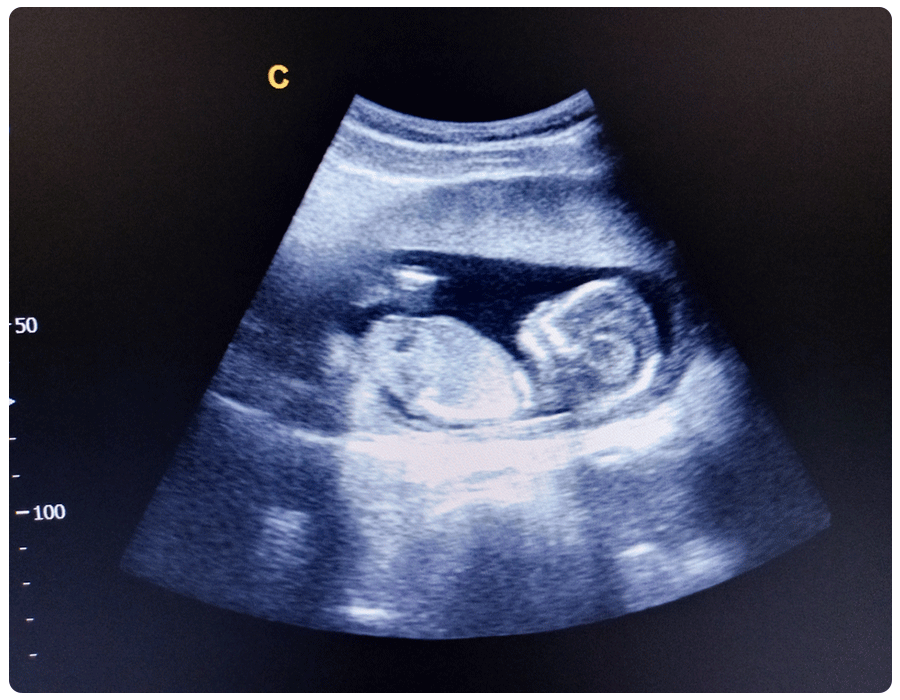

14-week ultrasound pictures

If you find yourself getting an ultrasound at 14 weeks, chances are high that you’ll get to go home with some pictures of your little one. Even better, baby will have an identifiable profile, so it’ll look like a real infant, not just an oddly shaped dark spot. Here’s an example of an ultrasound photo at 14 weeks.